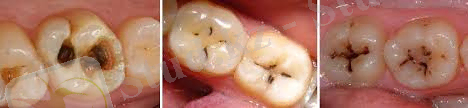

1. Бастапқы тісжегі - тістің сауыт беттерінде түсті дақ пайда болады. Алғашында ақшыл, беті жылтыр, кіреуке мөлдірлігі сақталған 1-2 мм болады. Сыртқы пішіні дөңгелек, сопақша, кейде күрделі пошымда болуы мүмкін. Сондай-ақ шекарасы анық келеді. Бірте-бірте шекара иір-қиыр болып шекарасы жойыла бастайды. Сосын кіреуке мөлдірлігі жойылып, дақ ақ-күңгірт түс иеленеді. Науқаста ешқандай субьективті белгілер болмайды. Кейде қышқыл әсерінен тістерде қармап қалу сезімі туындайды. Көбіне ауыз қуысын тексеріп зерттегенде анықталады. Кейде дақ сарғылт, қоңыр түске боялады. Мұны аурудың баяу дамыған түрі дейміз. Ал ақшылы-жедел дамығаны болады. Қара-қоңыр дақ көбіне тістің жанасу бетінде кездеседі. Қорытынды диагноз қою үшін бұл кеселді басқа дерттермен (гипоплазия, флюороз) салыстырып, ажырата білу керек. Қосалқы тексеру әдістері: дақтың бетін метилен көгінің ерітіндісімен бояу. Кариес дағы көк түске боялса, флюороз бен гипоплазия көк түске боялмайды (бұл кезде эрозияның өткізгіштік қасиеті төмен) .

2. Беткейлі тісжегі

1. субьективті белгілері: сырқат тіс химиялық, механикалық - тәттіден, ащыдан, қышқылдан ауырады.

2) көріп тексергенде тіс сауыты қуысының белгілі бетіндегі кіші тереңдікте 1 мм ойық анықталады.

3) шұқығанда қуыс қабырғасы тегіс емес, жұмсақ болады, табаны ауырады, қуыстың ауызы тар, табаны кеңдеу. Қорытынды диагноз қою үшін басқа аурулардан ажырата білу керек. а) гипоплазия - оның аяқша тәрізді түрі. б) флюороз - эрозиялы түрі в) сына тәрізді ақау г) тіс эрозиясы. Гипоплазия мен флюороздың ерекшелігі - ақаудың қабырғасы жылтыр, қатты болып шұқығанда ауырмайды. Сына тәрізді ақау мойнында орналасқан, қабырғалары жылтыр, шұқығанда, ащыдан, тәттіден ауыру сезімі болады. Тіс эрозиясында көбіне алдыңғы тістер жарақаттанады, ерін-жақ бетінде пайда болады. Қабырғасы жылтыр, тегіс. Ауыру сезімі химиялық әсерден пайда болады, симметриялы орналасады.